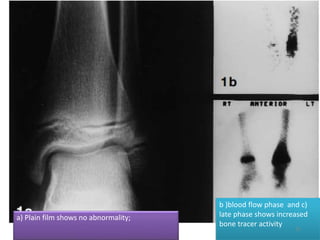

Radionuclide scanning:

• Should precede plain film examination in suspected

bone infection.

• Diagnosis can be confirmed as early as 48 hours after

the onset of the disease, even if clinical signs are

equivocal.

• This may help to initiate early aggressive treatment

to prevent gross bone destruction.

Radionuclides used:

• Tc 99m labelled phosphonates: most

commonly used

• Ga - 67 labelled citrate scan

• Indium-111 labelled WBC scan

a) Plain film shows no abnormality;

b )blood flow phase and c)

late phase shows increased

bone tracer activity

Tc - 99m scan

• 3 phase scan:

– Vascular flow phase (2-5 sec)

– Blood pool phase (5 min)

– Delayed phase (at 3-4 hours)

• In osteomyelitis, there is increased uptake noted in all the

three phases in the affected area.

• In cellulitis, increased uptake is seen in first two phases.